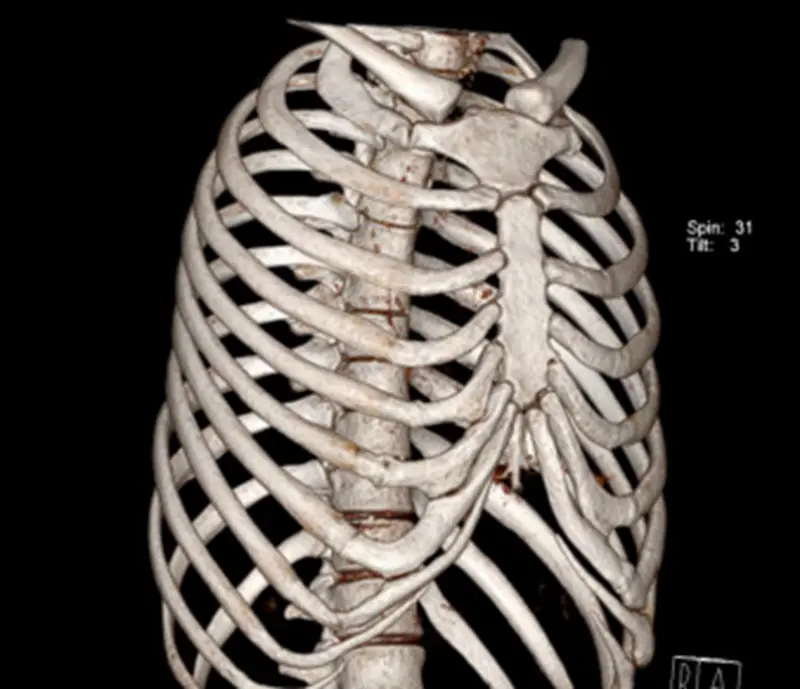

诊断骨关节外伤疾病哪家强 还看ct三维成像检查

诊断骨关节外伤疾病哪家强 还看ct三维成像检查 每日头条

骨关节外伤诊断哪家强 Ct三维成像有优势 北京安通医疗官网

肋骨骨折 你漏诊了吗 螺旋ct三维重建在胸廓骨折中的应用价值